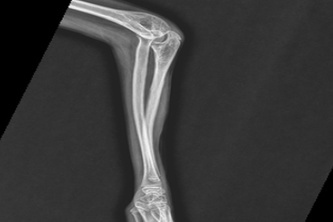

NanoScan: A Novel Tool For Detecting Hairline Fractures

This adaptive tool that diagnoses hairline fractures, small cracks in the bone that are undetectable to human eye, is a novel ML approach to diagnosing these fractures that become worse if untreated.